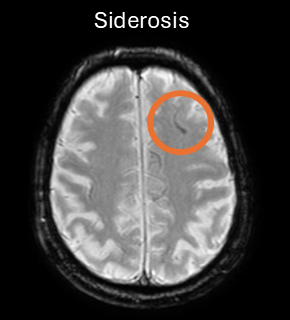

ARIA-H is characterized by small deposits of blood containing hemosiderin, which can either be parenchymal (microhemorrhages) or superficial siderosis in the pial or subarachnoid space. These changes can be detected as dark signal on susceptibility-sensitive sequences, such as T2* gradient echo (GRE) or susceptibility-weighted imaging (SWI).

ARIA-H rating is based on the classification of the number of new microhemorrhages. The categories may vary depending on drug and region, but typically are 0-4, 5-9 and 10 or more new microhemorrhages (excluding pre-existing ones). Superficial siderosis areas are usually counted individually and not grouped, given their greater clinical relevance.

| ARIA-H (new superficial siderosis) | 1 focal area | 2 focal areas | ≥ 3 focal areas |